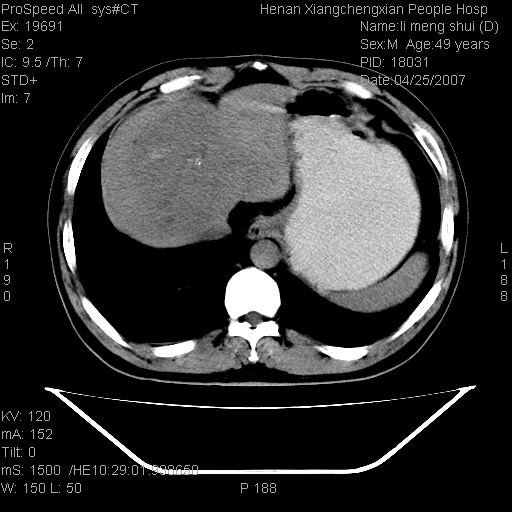

| 患者,男,49岁, 腹疼伴恶心\\呕吐20天,20天前无明显诱因出现右上腹部疼痛,钝疼,无放射,伴恶心\\呕吐,不伴发热.患者不愿增强. b超:肝脏右叶实性占位. ct:肝脏右叶可见一巨块状圆形低密度影,大小约93mm*84mm,其内可见点状高密度影,胆囊、胰腺、脾脏大小、形态及密度未见异常,腹膜后间隙未见肿大淋巴结影。 印象:肝脏右叶巨大肿块,性质待定,建议增强并穿刺活检进一步确诊。 ct平扫: ![]() ![]() ![]() ![]() ![]() ![]() ![]() ![]() ![]() ![]() ![]() ![]() ![]() ![]() ![]() ![]() ![]() 肝脏右叶肿块ct引导下穿刺活检术 患者于16时05分仰卧于ct检查台上,首先行肝脏ct扫描确定进针位置、深度、角度。在局麻下行ct引导下肝脏右叶肿块穿刺活检术。常规消毒、铺巾、局麻。在ct引导下使活检针经右侧腋中线、第9肋间隙垂直胸壁进针90mm,针头进入病变预定位置。在病变预定位置多点、多方向抽取小米样病变组织多块,涂片五张送病理检查。术后穿刺点局部无出血,未出现腹腔积液等并发症。术中及术后患者生命体征稳定,手术于17时10分成功完成。患者安返病房。 穿刺片 ![]() ![]() ![]() ![]() ![]() ![]() ![]() ![]() ![]() ![]() ![]() ![]() ![]() ![]() ![]() ![]() 病理结果肝细胞癌 ![]() 原贴地址:http://www.radinet.com.cn/forum_view.asp?forum_id=4&view_id=24130 ok |